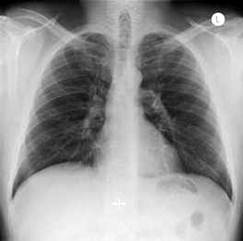

7. Легкие живого человека

А) Б)

Рис 1. Рентгенограммы легких: а) взрослого мужчины; б) ребенка.

При рентгенологическом исследовании грудной клетки ясно видны два светлых Вллегочных поляВ», по которым судят о легких, так как вследствие наличия в них воздуха они легко пропускают рентгеновские лучи и дают просветления. Оба легочных поля отделены друг от друга интенсивной срединной тенью, образуемой грудиной, позвоночником, сердцем и крупными сосудами. Эта тень составляет медиальную границу легочных полей; верхняя и латеральная границы образованы ребрами. Снизу находится диафрагма.

Верхняя часть легочного поля пересекается с ключицей, которая отделяет надключичную область от подключичной. Ниже ключицы на легочное поле наслаиваются пересекающиеся между собой передние и задние части ребер. Они располагаются косо: передние отрезки тАУ сверху вниз и медиально; задние тАУ сверху вниз и латерально. Хрящевые части передних отрезков ребер при рентгеновском исследовании не видны. Для определения различных пунктов легочного поля пользуются промежутками между передними отрезками ребер (межреберья).

Собственно легочная ткань видна в светлых ромбовидных межреберьях. В этих местах виден сетевидный или пятнистый рисунок, состоящий из более или менее узких тяжеобразных теней, наиболее интенсивных в области корней легких и постепенно убывающих в своей интенсивности от срединной тени сердца к периферии легочных полей. Это так называемый легочный рисунок. По обе стороны тени сердца на протяжении передних отрезков II тАУ V ребер располагаются интенсивные тени корней легких. От тени сердца они отделены небольшой тенью главных бронхов. Тень левого корня несколько короче и уже, так как она больше прикрывается тенью сердца, чем справа.

Анатомической основой тени корней и легочного рисунка является сосудистая система малого круга кровообращения тАУ легочные вены и артерии с радиарно отходящими от них ветвями, рассыпающимися в свою очередь на мелкие веточки. Лимфатические узлы в норме не дают тени.

Анатомический субстрат легочного рисунка и теней корней особенно ясно заметен при томографии (послойной рентгенографии), которая дает возможность получить снимки отдельных слоев легкого без наслоения на легочное поле ребер. Легочной рисунок и корневые тени есть симптом нормальной рентгеновской картины легких в любом возрасте, включая и ранний детский. При вдохе видны просветления, соответствующие плевральным синусам.

Рентгенологический метод исследования позволяет видеть изменения в соотношениях органов грудной клетки, происходящие при дыхании. При вдохе диафрагма опускается, куполы ее уплощаются, центр передвигается несколько книзу. Ребра поднимаются, межреберные промежутки делаются шире, Легочные поля становятся светлее, легочный рисунок отчетливее. Плевральные синусы ВлпросветляютсяВ», становятся заметными. Сердце приближается к вертикальному положению. При выдохе возникают обратные соотношения.